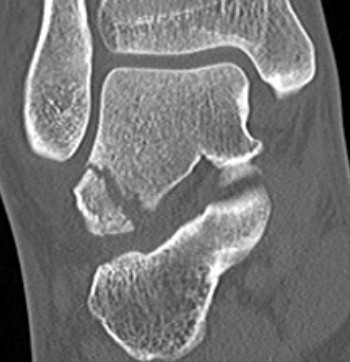

CT

McCrory-Bladin Classification

| Type I |

Type 2A |

Type 2B | Type 3 |

|---|---|---|---|

|

Chip fracture Doesn't involve articular surface |

Larger fracture Involves articular surface talofibular & subtalar join Undisplaced |

Larger fracture Involves articular surface talofibular & subtalar joint Displaced |

Comminuted fracture Involves articular surface talofibular & subtalar |